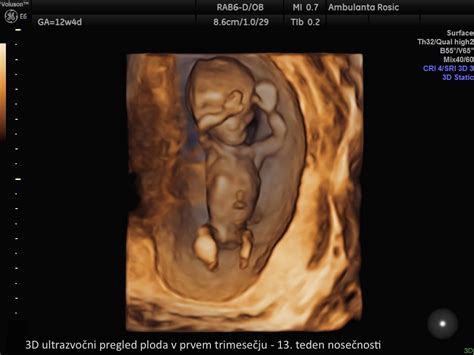

Ultrazvok in Medicinski Pregledi

Ultrazvok v 14. tednu nosečnosti je pomembno orodje za spremljanje razvoja ploda. Poleg že omenjenega določanja spola, ultrazvok prikaže plod, ki se aktivno premika. S pomočjo sodobnih ultrazvočnih tehnologij, kot je barvni Doppler, lahko zdravniki prikažejo izvor in potek popkovnice s tremi žilami (eno veno in dvema arterijama), ter ocenijo njeno debelino, ki je v tem tednu okoli 5 mm. Pogled na plod s hrbtne strani omogoča oceno razvoja hrbtenice.

Ultrazvočni pregledi potekajo med 8. in 14. tednom nosečnosti, zato bi moral biti prvi pregled opravljen do 14. tedna. Ti pregledi z uporabo neškodljivih zvočnih valov izrišejo natančno sliko vašega otroka v maternici.